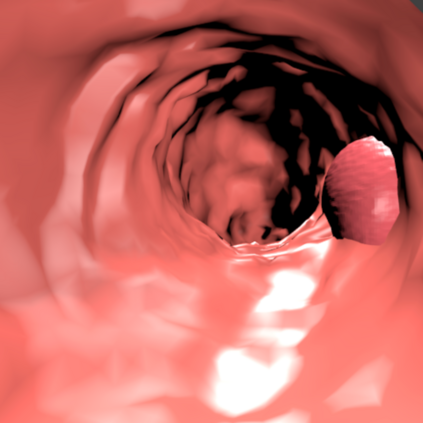

Deep learning has shown excellent performance in analysing medical images. However, datasets are difficult to obtain due privacy issues, standardization problems, and lack of annotations. We address these problems by producing realistic synthetic images using a combination of 3D technologies and generative adversarial networks. We use zero annotations from medical professionals in our pipeline. Our fully unsupervised method achieves promising results on five real polyp segmentation datasets. As a part of this study we release Synth-Colon, an entirely synthetic dataset that includes 20000 realistic colon images and additional details about depth and 3D geometry: https://enric1994.github.io/synth-colon